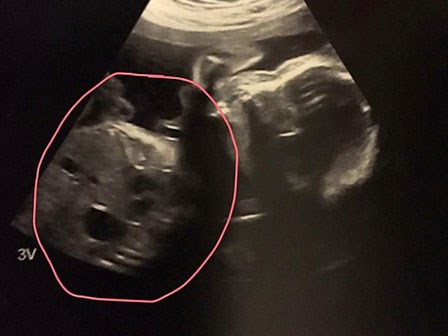

Đang siêu âm thai, cặp đôi bị sốc khi nhìn thấy hình ảnh xuất hiện trên màn hình

Bên cạnh khuôn mặt thai nhi là hình ảnh vô cùng lạ khiến ai cũng ngỡ ngàng.